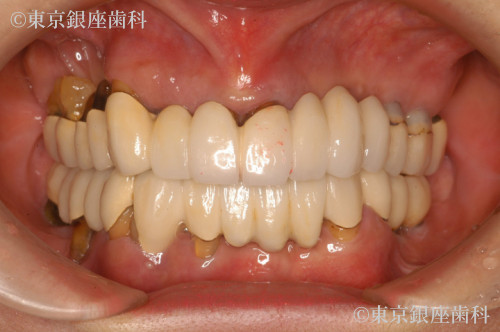

After

過去の高額ブリッジ治療が数年で崩壊し不安を抱えて来院。部分インプラント後、上下ワンデイへ移行。サイナスリフトも併用し安定した噛み合わせを獲得。

上下ワンデイインプラント+サイナスリフト